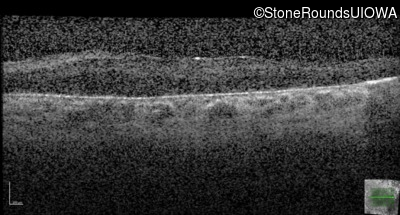

Optical Coherence Tomography - Right - 20/250 sc

Exemplar / OCT Stack

OCT Stack